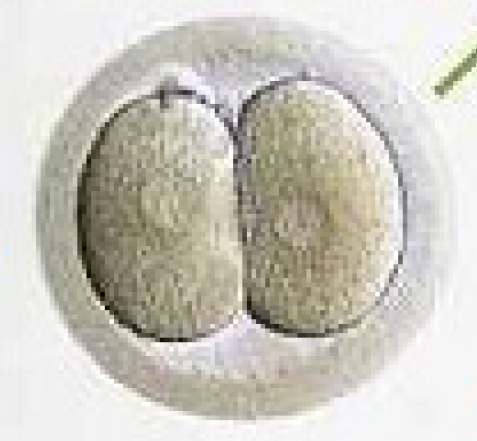

Figuur 7. Ontwikkeling van een embryo.

Dag 3.

8-cellig embryo.

Dag 2.

4-cellig embryo.

Dag 1.

2-cellig embryo.

Dag van de punctie.

Bevruchte eicel.